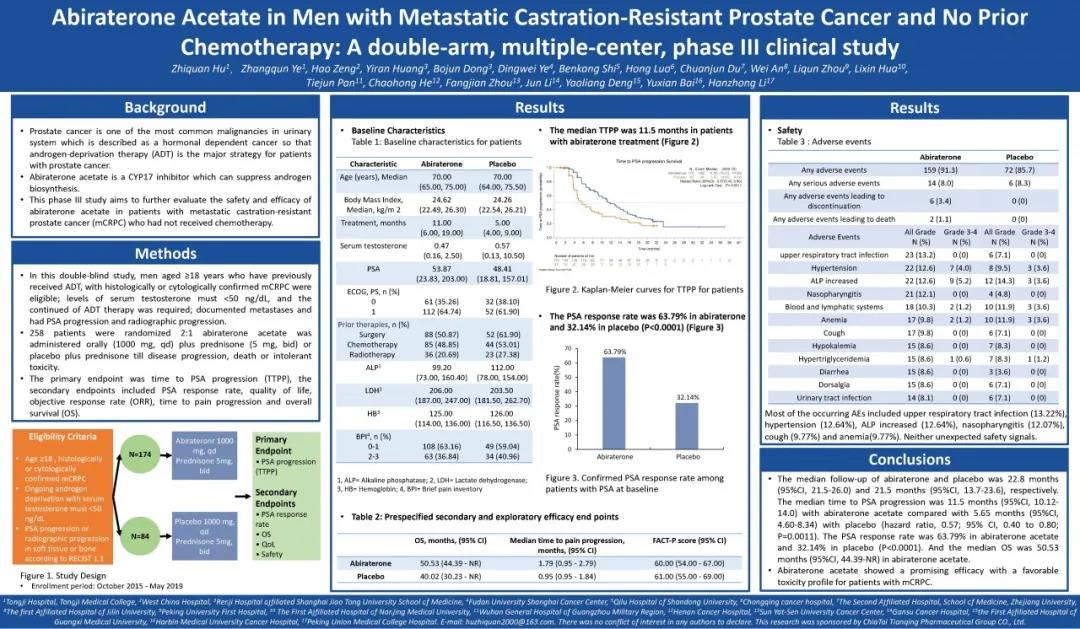

前列腺癌,是全球男性第二大常见癌症。随着新的内分泌治疗、细胞毒性的化学治疗、免疫治疗等疗法的逐步问世,为患者提供了更多的治疗选择。多项研究确定的基因图谱特征,也鉴...